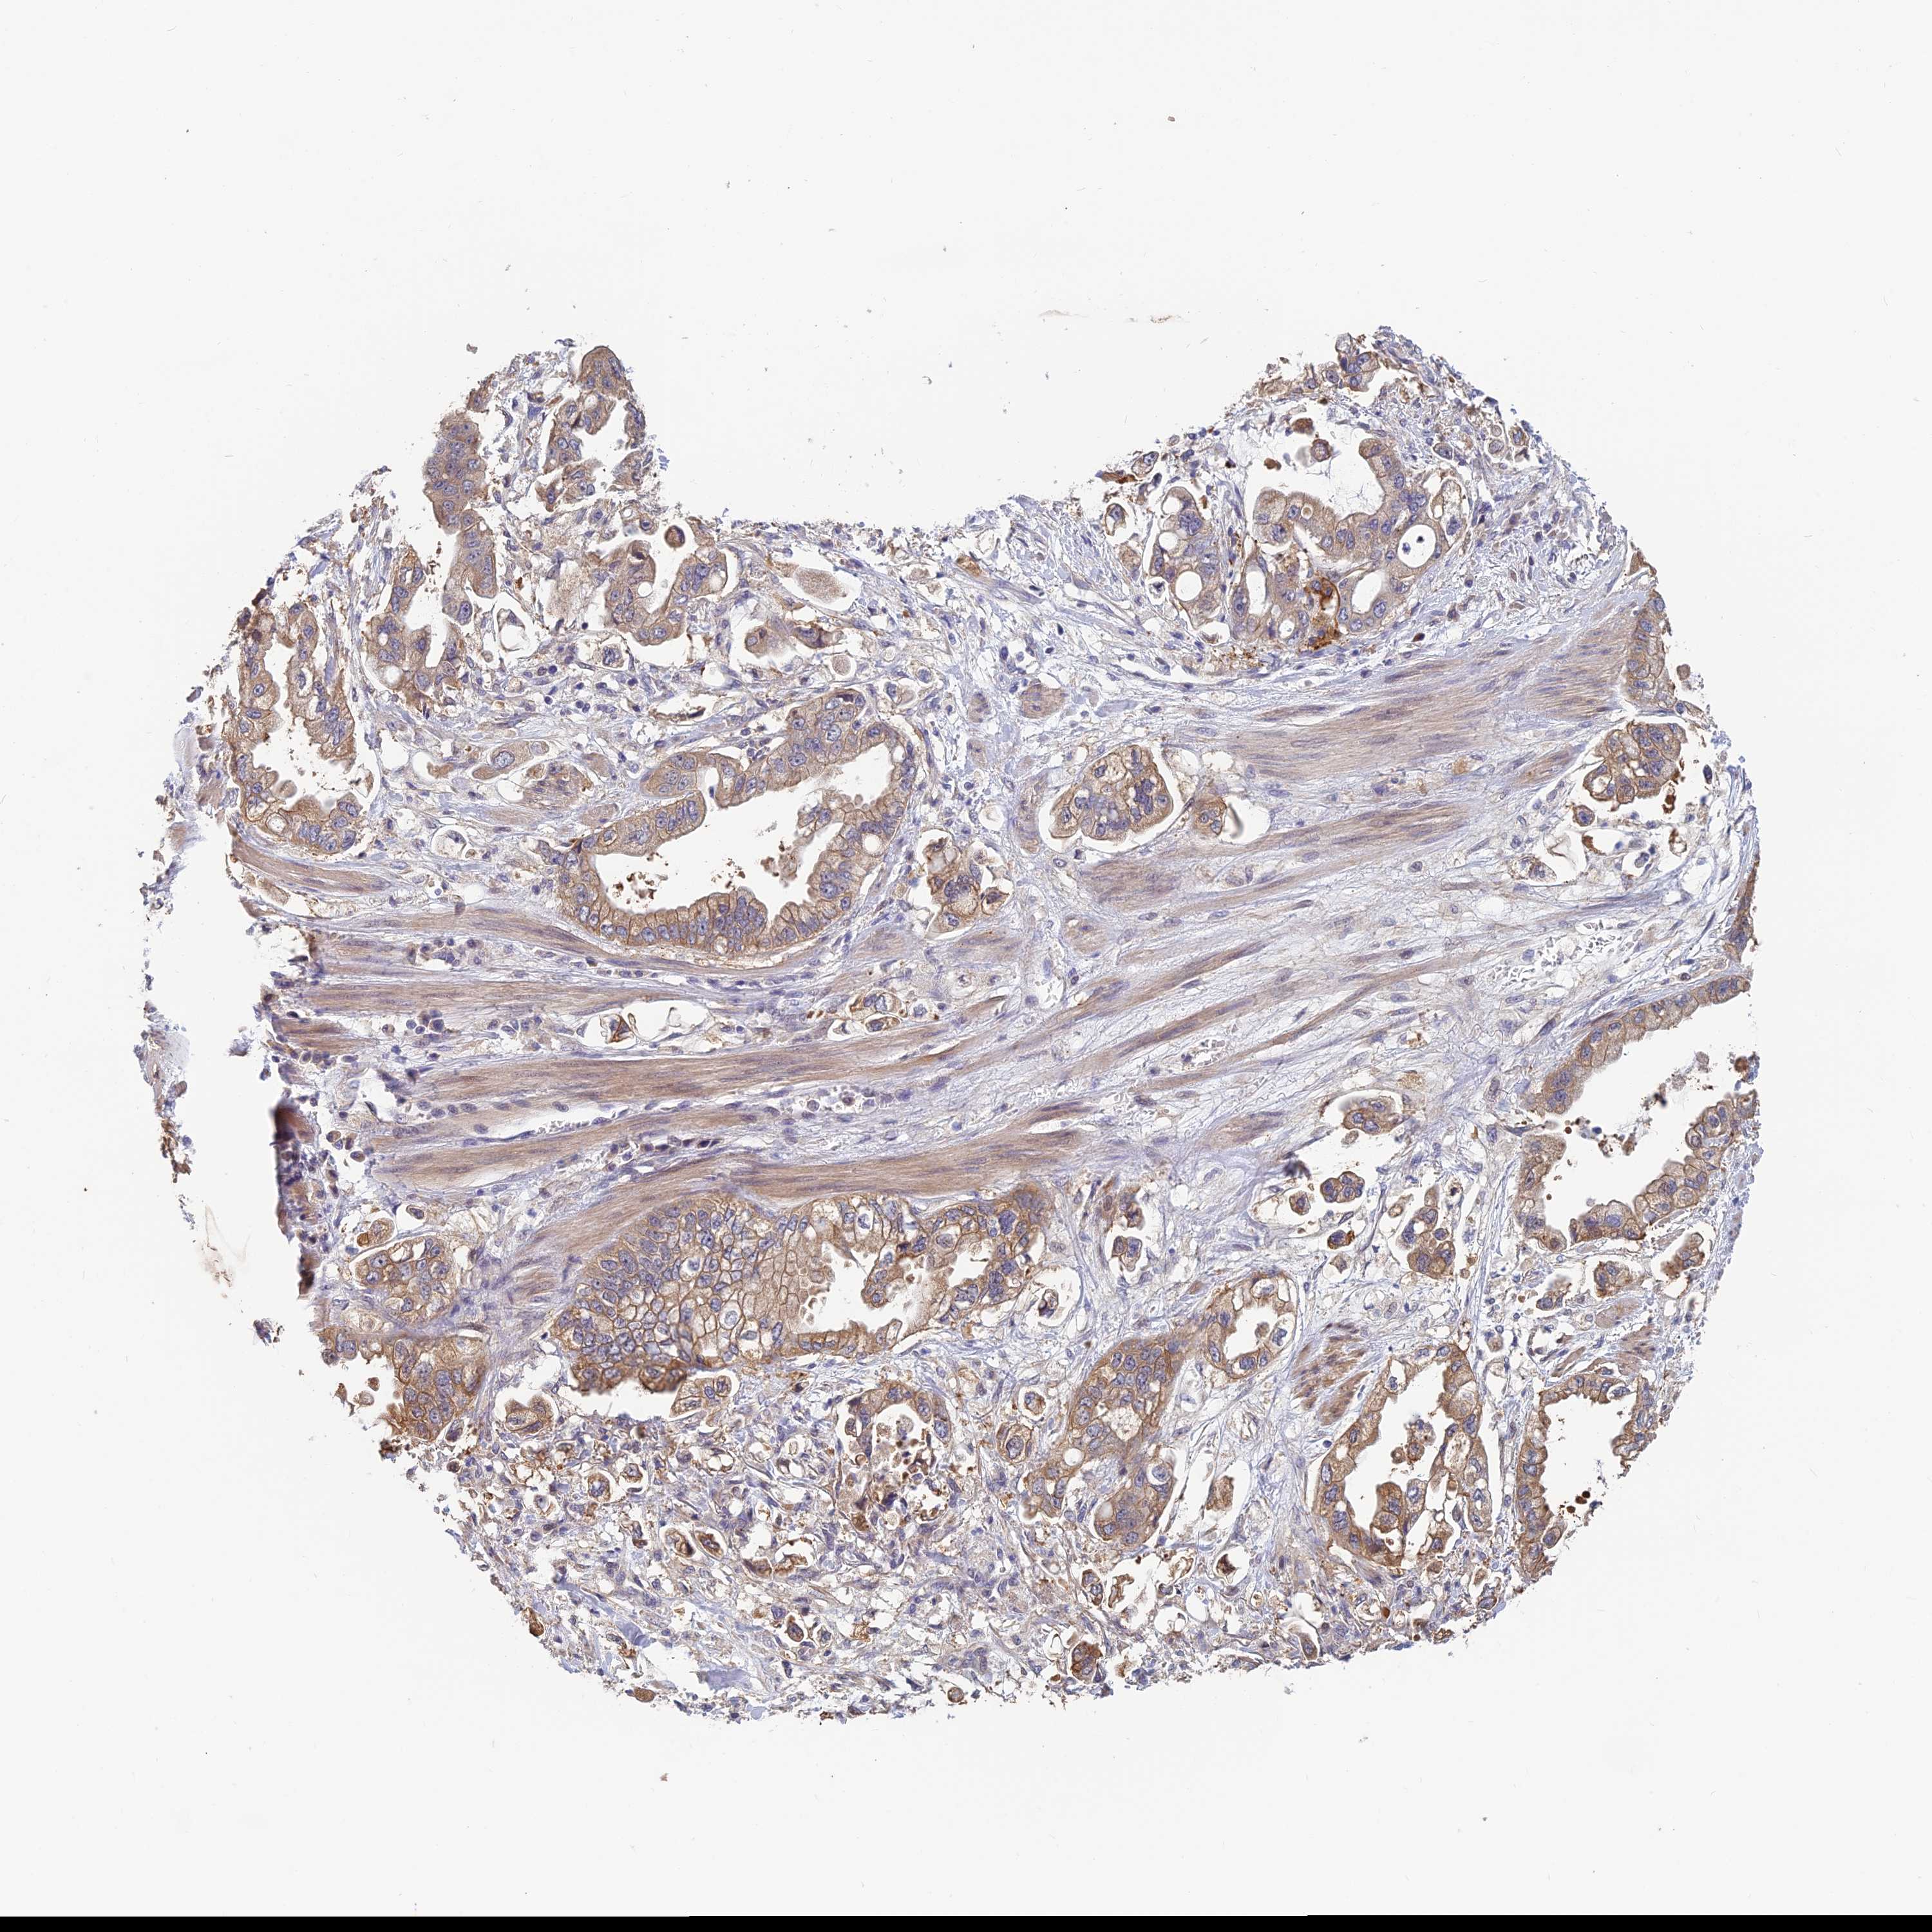

STOMACH CANCER - Protein expressioni

A mouse-over function shows sample information and annotation data. Click on an image to view it in a full screen mode. Samples can be filtered based on level of antibody staining by selecting one or several of the following categories: high, medium, low and not detected. The assay and annotation is described here.

Antibody stainingi

Antibody staining in the annotated cell types in the current human tissue is reported as not detected, low, medium, or high, based on conventional immunohistochemistry profiling in selected tissues. This score is based on the combination of the staining intensity and fraction of stained cells.

Each image is clickable and will lead to virtual microscopy that enables deeper exploration of all samples and also displays staining intensity scores, fraction scores and subcellular localization as well as patient and tissue information for each sample.

Antibody HPA042313

Staining

High

Medium

Low

Not detected

Intensity

Strong

Moderate

Weak

Negative

Quantity

>75%

75%-25%

<25%

None

Location

Nuclear

Cytoplasmic/membranous

Cytoplasmic/membranous,nuclear

Adenocarcinoma, NOS